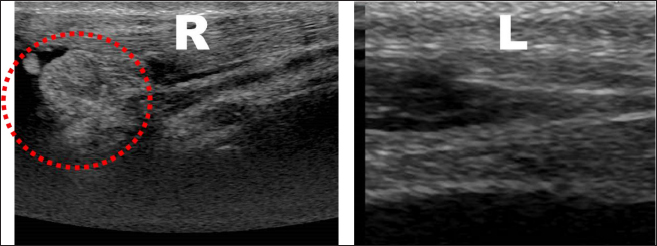

On examination at our hospital, a Monroe walk was observed, with a Grade I lameness score of the right hind limb. On orthopedic examination, swelling, and warmth of the right tarsal joint were observed, as well as crepitus and pain during extension and flexion. Lateral mobility of the Achilles tendon attachment was observed when the affected limb was flexed. Radiographic examination showed increased soft tissue opacity around the caudal aspect of the right calcaneus (Fig. 1). Ultrasonography revealed a hyperechoic structure and fluid retention around the right Achilles tendon (Fig. 2). Based on these observations, we diagnosed lateral luxation of the SDF. Presurgical medication consisted of continuous infusion of butorphanol (0.2 mg/kg intravenously), medetomidine (2 μg/kg intravenously), and lidocaine (1 mg/kg intravenously). In addition, robenacoxib (2 mg/kg) was administered subcutaneously for analgesia. Ropivacaine (3 mg/kg) was administered for the sciatic nerve block. Intravenous propofol (6 mg/kg) was administered for the induction of anesthesia, and anesthesia was maintained with oxygen-sevoflurane. The overall general anesthesia time was 91 minutes, and the operation time was 68 minutes. The collected joint fluid was serous, and postoperative Diff-Quick staining showed a large number of macrophages, suggesting chronic inflammation (Fig. 3A). Medial capsulorrhaphy of the tarsal joint, arthrodesis, in which the shallow digital flexor tendon was sutured with 2–0 polydioxanone, and fixation with a 1.5-mm Kirschner wire were performed (Figs. 3B and 4A). Postoperatively, the tarsal joint was stretched to prevent tension on the tendon. A cast made of Castrolite Alpha® (ALCARE Corporation, Tokyo, Japan) was applied without the cranial aspect; and the Robert Jones bandage technique was used for stabilization (Fig. 4B). Postoperative medication consisted of intravenous cefazolin (20 mg/kg), subcutaneous sodium carbazochrome sulfonate (0.5 mg/kg), and tranexamic acid (10 mg/kg) twice daily for 3 days. Cefazolin (20 mg/kg twice daily) was also administered until suture removal. The Robert Jones bandage was removed on postoperative day 28. Finally, we removed the pin on postoperative day 88 under general anesthesia using the same methods as previously described. The patient walked well without pain and lameness 12 days after the removal of the pin.

Fig. 2. Ultrasonography showing a bumpy hyperechoic structure and fluid retention around the right Achilles tendon.